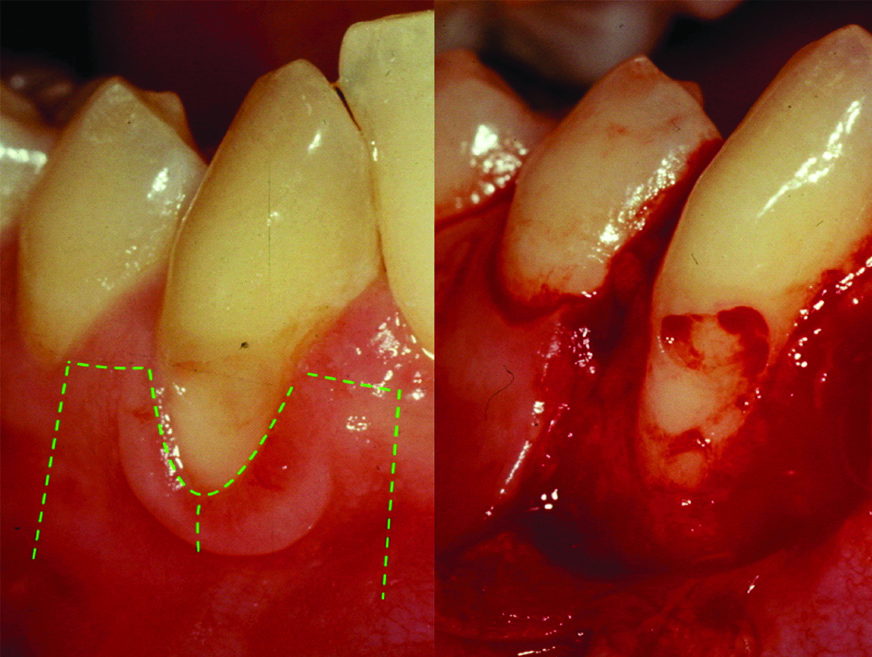

A 36-year-old female patient presented in to the periodontal clinic in 2002 with a complaint of long teeth and sensitivity in the lower right (#43) and left (#33) canines. The dental history revealed that the patient had a history of using an aggressive brushing technique, which caused generalised abrasion of the cervical region and resulted in the placement of a composite restoration to fill the abrasion area. Subsequently, gingival recession occurred in some areas, and root sensitivity reoccurred because of a leakage of these restorations. Clinical examination revealed the presence of gingival recessions of approximately 3-4 mm on teeth #33 and #43, with the presence of a composite restoration on the root surface [Table/Fig-1]. The recession defect was classified as Miller’s Class II, with 1 mm of a keratinised gingiva and no attached gingiva [1]. The probing depth ranged from 1 to 2 mm. The plaque index was 75%, with bleeding on probing of 55%. Phase I therapy consisted of scaling and root planing, with plaque control measures using a modified Stillman’s brushing technique and interdental flossing at home. The surgical phase consisted of removal of the old restoration and replaced with a new restoration which; was contoured to the crown only then, placement of a connective tissue graft, combined with a double-papilla flap. The patient agreed to the procedure and signed informed consent. Prior to soft tissue grafting, the composite restoration was removed from the root surface and contoured to the tooth crown only, and the root surface was smoothed with a finishing bur [Table/Fig-2]. The right side of the palate was used as a donor site, which was anaesthetised with one ampoule of lidocaine, while each recipient site received two ampoules. Blade #15 was used for incision placement and palatal tissue harvesting. Two oblique incisions of 3 mm long were placed on each side of the tooth, with two vertical incisions extended beyond the mucogingival junction. A partial thickness flap was utilised all the way long [Table/Fig-3]. A connective tissue graft of 13×5 mm, with 2-mm thickness after removal of adipose tissue, was harvested from the palate, and the donor site was secured with a 4-0 vicryl suture [Table/Fig-4]. The graft was divided in half, for teeth #33 and #43, respectively. The graft was then, sutured in place with a 5-0 vicryl suture using a simple interrupted technique; then, a double-papilla rotational flap was secured with 5-0 vicryl [Table/Fig-5]. No periodontal dressing was used. Postsurgical medication consisted of ibuprofen 400 mg/qid for four to seven days and rinsing with normal saline twice daily for seven days. The patient was instructed to eat soft food for seven days. Brushing of the surgical site was deferred for six weeks, and the patient was asked to use a cotton tip with mouthwash to clean the area twice daily. The sutures were removed after two weeks, and the healing was uneventful, with no complications [Table/Fig-6]. Since the patient had mild localised periodontitis, with a history of an aggressive brushing technique, she was placed on a maintenance recall every four months for suppurative periodontal therapy.

Pre-operative images for teeth #43 and #33 in 2002.

Image after composite removal from teeth #43 and #33 and root surface smoothening.